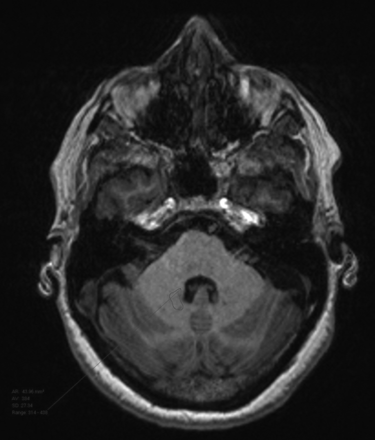

Two radiologists conducted a quantitative analysis of unenhanced T1-weighted images using ROI measurements. Measurements were made on the baseline scan and the seventh scan. In keeping with previously described techniques, ROIs were drawn over the left globus pallidus, dentate nucleus, lateral ventricle, and pons, and average signal intensity was recorded.12,19 Examples of ROI selection are presented as Figs 1⇓–3. We compared DN and GP signal intensities with T1 measurements of the pons and calculated the ratios of these intensities: dentate nucleus/pons (DN/pons) and globus pallidus/pons (GP/pons).12 If the left side could not be evaluated due to artifacts or pathology, the right side was used.

Dentate nucleus ROI selection.